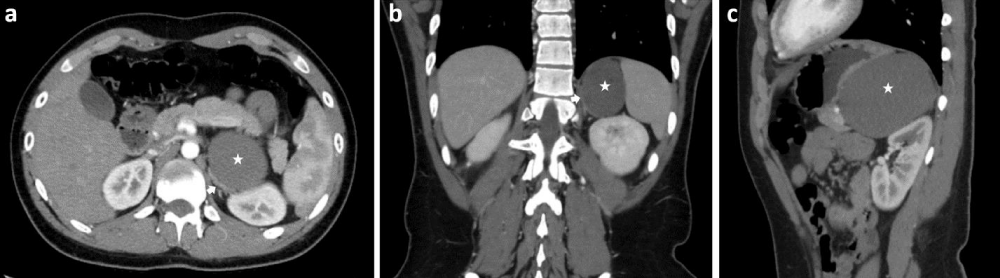

CT scans are more frequently the first imaging modality owing to their faster image acquisition. Retroperitoneal bronchogenic cyst presents as homogenously hypoattenuating, non-enhancing, sharply defined spherical lesions with well-circumscribed smooth or lobulated borders (Figure 2). Retroperitoneal bronchogenic cysts normally contain water and proteinaceous mucus, with possible remnants of prior hemorrhage or infection. This leads to attenuation that is more comparable to that of water (0-20 HU) following intravenous contrast. However, the cyst may contain thick mucinous or proteinaceous secretions, active hemorrhage, or calcification, that will result in hyperattenuation with coefficients of up to 120 HU. This hyper attenuation may result in the cyst being misdiagnosed as a solid structure. Occasionally a fluid-fluid level may form as a result of the higher viscosity fluid settling at the bottom of the cyst. Overall a complete adrenal structure, fusiform appearance, and calcification within a cystic lesion in the adrenal region are indicative of a retroperitoneal bronchogenic cyst. Unfortunately, a CT scan alone may not be able to provide adequate information regarding lesions that lack internal heterogeneity or mural enhancement [1,2,5].

Download Image

Figure 2: Contrast enhanced CT of the abdomen in the axial (a), coronal (b) and sagittal (c) planes showing a left retroperitoneal suprarenal cyst (star) pushing the left kidney posteroinferiorly, the left adrenal gland (a, b; white arrow) medially, and the stomach superoanteriorly. The cyst is adjacent to the left adrenal gland, pancreas, and stomach. There is no fat tissue between them.